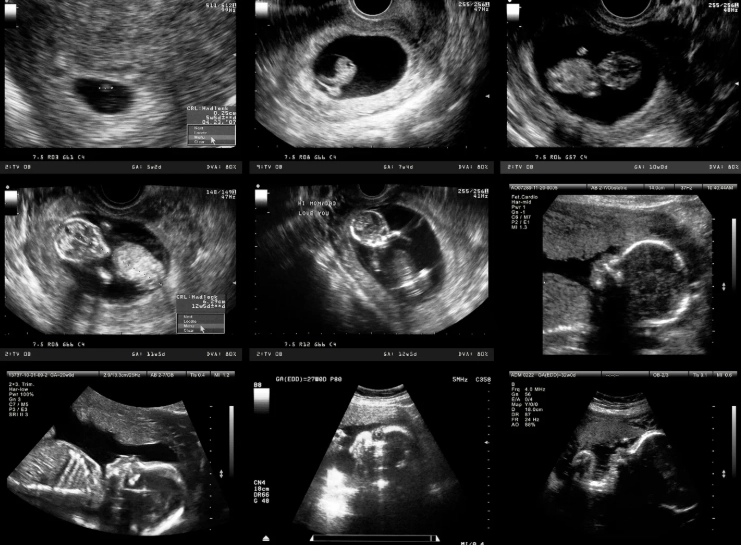

This is the core of it, right? You want to know if you'll see a little bean, a heartbeat, something that makes it feel "real." At one month pregnant (or about 4 weeks gestational age), the embryo is incredibly tiny – we're talking about the size of a poppy seed. It's just beginning to implant and grow.

So, an ultrasound this early is often a transvaginal one (where a probe is inserted into the vagina). It gets a closer, clearer view than an abdominal scan. Here's the breakdown of what a sonographer or doctor is typically looking for at this stage:

| Gestational Sac | Maybe, just barely. | This is the first structure to become visible. It's a small, fluid-filled sac that surrounds the embryo. It might be seen as a tiny black dot in the uterus. If it's not seen, it could simply be too early. |

| Yolk Sac | Very rarely. | This sac provides early nourishment. It usually appears inside the gestational sac around 5-5.5 weeks. Seeing it at a true 4-week scan would be highly unusual and might indicate dating is off. |

| Fetal Pole (the embryo itself) | Almost never. | The actual embryo is microscopic. It typically becomes visible on ultrasound around 6 weeks. |

| Heartbeat | No. | The heart is just beginning to form from cells. Cardiac activity usually becomes detectable via ultrasound around 6 weeks, and even then, it's not always clear. |

| Location of Pregnancy | Yes, this is key. | The most critical job of an early scan is to confirm the pregnancy is inside the uterus (intrauterine). This rules out an ectopic pregnancy, which is a serious medical condition. |

See what I mean? The pickings are slim. A lot of reputable sources, like the American College of Obstetricians and Gynecologists (ACOG), generally don't recommend routine ultrasounds this early unless there's a specific medical reason. The reason is simple: there's often not enough to see to provide reassurance, and it can sometimes lead to more anxiety if things aren't perfectly clear (which is common).